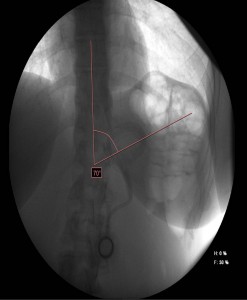

Tránsito esofagogastroduodenal: Banda gástrica malposicionada, localizada aproximadamente a 5-6 cm de la unión esofagogástrica con ángulo phi aumentado de 70º (normal de 4 a 58º). Marcada dilatación del bolsón proximal, con paso enlentecido, filiforme del contraste a través de la banda, no objetivándose paso distal hasta los 10 minutos y persistiendo más allá de los 45 minutos del comienzo del estudio.